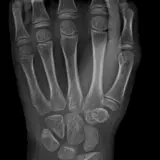

Over 2,100 interactive radiology cases, curated by radiologists for your level of training. Scroll, window, and view cases full screen — just like on PACS. Click linked findings in each writeup to jump straight to them on the image. Cases include sample reports, a focused discussion section, original illustrations, and videos.

PACSで期待されるツールを完備した完全インタラクティブな症例 — スクロール、ウィンドウ調整、ズーム、パン、計測、ROI、フルスクリーンモード。

重要な所見を症例画像上に直接ハイライトする豊富なアノテーション。症例解説内のリンクされた所見をクリックすると、スキャン上の正確な位置へジャンプできます。